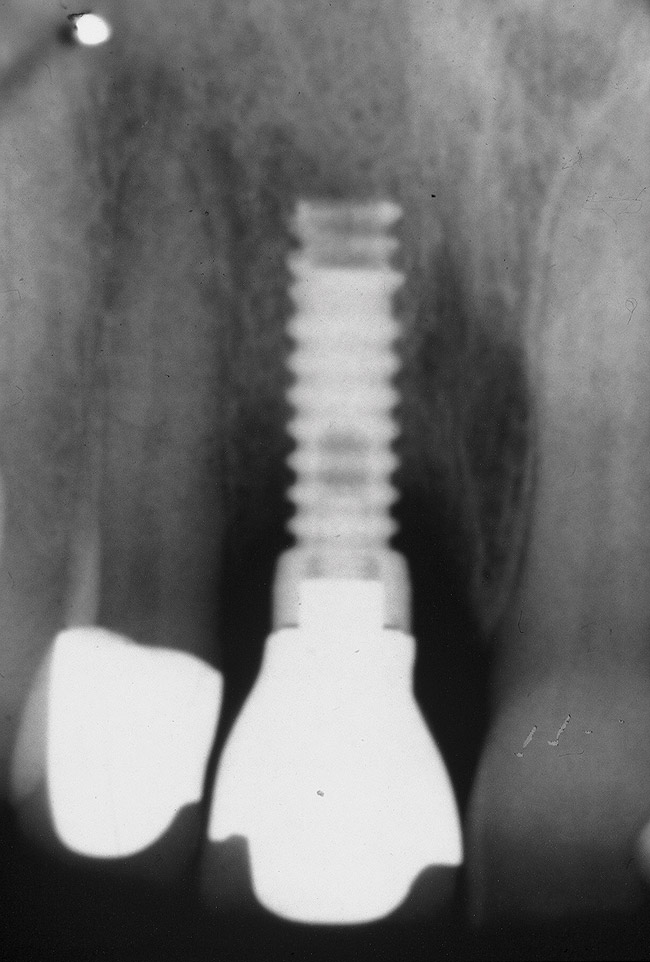

The patient returned regularly for recall visits for 7 years, but then did not return for follow-up or maintenance for 2 years. He then returned for evaluation and retreatment of the implant. However, retreatment was not possible as the bone loss and lesion morphology were unfavorable for attempting a regenerative approach (Figure 14). The implant was removed atraumatically, and the site was grafted with a composite graft of mineralized and demineralized freeze-dried bone allograft and covered with an absorbable porcine collagen barrier. The flap was advanced to enable primary closure of the site and it was allowed to heal for 6 months. Re-entering the site, the bone fill achieved by the regenerative efforts enabled a second implant to be placed in a favorable prosthetic position (Figure 15 and Figure 16).

Figure 16  Radiograph 1 year following final restoration showing stable peri-implant bone levels.

Figure 16